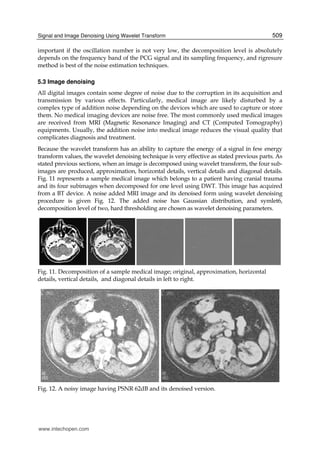

Quantitatively assessing the performance in practical image application is complicated issue

because the ideal image is normally unknown. Therefore the rational approach is to use

known images for the tests, as in other image processing applications, in order to test the

performance of the wavelet denoising methods like one dimensional signal denoising.

Figure 13 represents the medical test images to be used.

Here, we use again a classical comparison receipt based on noise simulation. The comparison

can be realized on the result reconstructed image and the original image after adding Gaussian

white noise with known power to the original signal. Then it will be computed the best image

recovered from the noisy one for each method. Firstly, we should determine the effective

decomposition level because the most important factor in wavelet denoising is decomposition

level. For this purpose, a noise added image will be used to obtain how the performance is

changing respect to the decomposition level. The recovering process is made on the test image

given in Fig 11, on which a Gaussian noise added to be PSNR is 62dB. The noisy image and a

sample recovered or denoised is given Fig. 12a and Fig. 12b, respectively. The PSNR values

after denosing process is given Table 3. In this denoising process, the symlet6 and universal

thresholding is chosen as mother wavelet and noise level estimator.

Fig. 12. Medical test images.

Level PSNR

1

2

3

4

5

6

7

8

9

10

68.1196

69.3269

70.5006

70.7768

68.6232

68.8183

68.7272

69.8037

66.8912

66.3877

Table 3. PSNR values respect to decomposition level after DWT denoising.